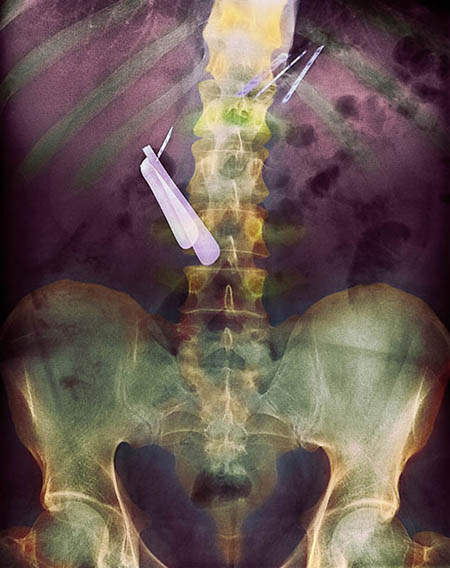

因為手術,而被留在患者體內的剪刀